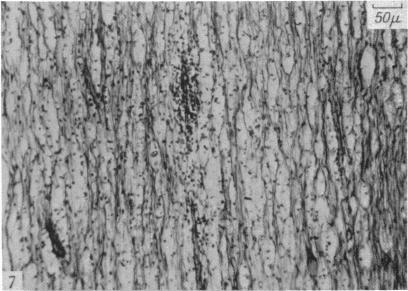

The degeneration and re-innervation of grafted nerves.

J Anat. 1942 Jan;76(Pt 2):143-166.7.